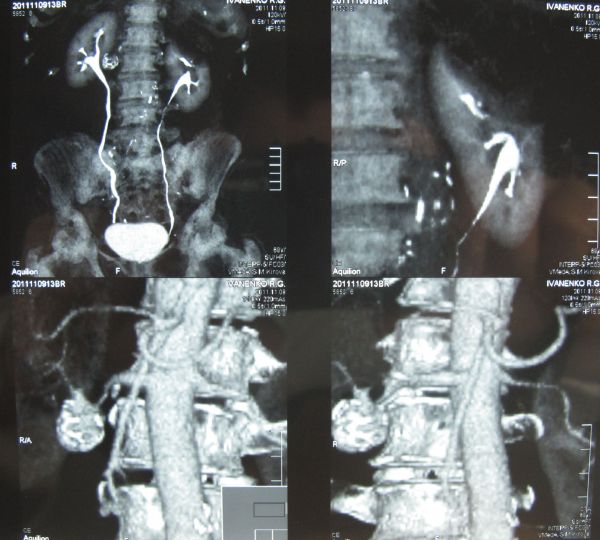

Аневризма почечной артерии